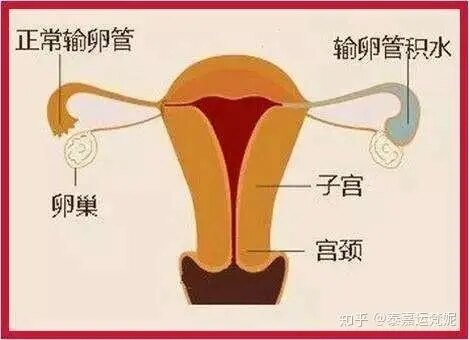

1.输卵管积水:看到宫腔积液首先想到的就是输卵管积液了,输卵管和宫腔相连,如城门失火殃及池鱼一般,促排中输卵管积水因为雌激素过高会更加肿胀,积液从输卵管逆流进入宫腔,形成宫腔积液。在输卵管因素不孕中的宫腔积液占到7.7-15.2%。一旦有输卵管积水引起的宫腔积液会使得试管婴儿成功率大大下降!

输卵管积水引起的宫腔积液:可能使得移植成功率下降20%-30%,所以一定要处理!方法很多:可以x光下或宫腔镜下输卵管近段栓堵,可以夹闭或者结扎输卵管,甚至可以切除输卵管。需要提醒的是务必找输卵管手术熟练的医生做,因为这样的医生懂得保护您的卵巢血供,手术引起的卵巢功能减退真的令人痛心,杀敌一千自损八百不合算。

实在不愿意手术的患者还可以尝试B超引导下输卵管积液的抽吸术,据说有一定效果,但本人尝试下来效果不理想,复发率很高。